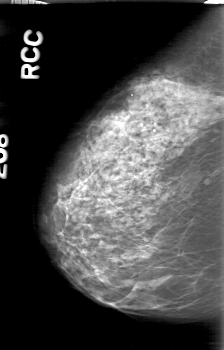

D_4164_1.RIGHT_MLO

D_4164_1.RIGHT_CC

RIGHT_CC LINES 5236 PIXELS_PER_LINE 3346 BITS_PER_PIXEL 12 RESOLUTION 43.5 NON_OVERLAY

RIGHT_MLO LINES 5266 PIXELS_PER_LINE 3406 BITS_PER_PIXEL 12 RESOLUTION 43.5 NON_OVERLAY